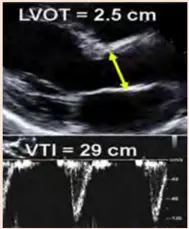

- Measurement of the AR peak velocity and VTI by CWD allows calculation of the EROA and RVol

- The threshold for severe AR is an EROA ≥0.30 cm^2 and an RVol > 60 mL